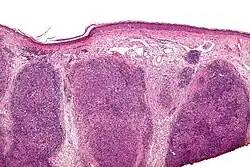

| Low magnification micrograph of a lymphoepithelioma-like carcinoma showing the characteristic squamoid nests in association with clusters of lymphocytes. H&E stain. | |

Lymphoepithelioma-like carcinoma (LELC) is a medical term referring to a histological variant of malignant tumor arising from the uncontrolled mitosis of transformed cells originating in epithelial tissue (or in cells that display epithelial characteristics) that bear microscopic resemblance to lymphoepithelioma (nasopharyngeal carcinoma).